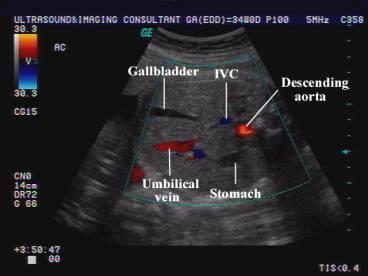

When is the GB seen?

20 weeks

Fetal GB

Fetal GB

Fetal GB

What is the AC landmarks?

trans spine - 3 oss center

J - portal vein

stomach & GB